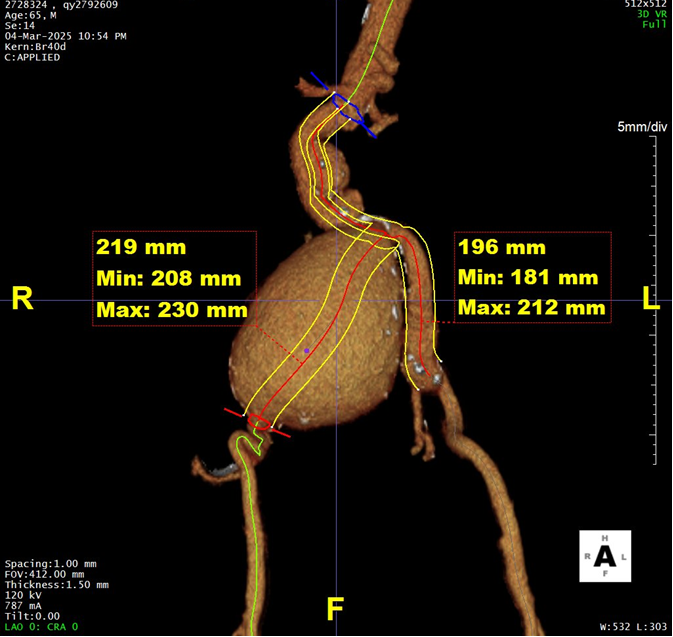

二、术前CTA详解

gore医疗怎么样「漫腹精论」髂合时宜 精益求精——双MOB球囊导管辅助腹主动脉覆膜支架急诊治疗破裂巨大髂动脉瘤_https://www.jmylbn.com_新闻资讯_第5张

gore医疗怎么样「漫腹精论」髂合时宜 精益求精——双MOB球囊导管辅助腹主动脉覆膜支架急诊治疗破裂巨大髂动脉瘤_https://www.jmylbn.com_新闻资讯_第6张

gore医疗怎么样「漫腹精论」髂合时宜 精益求精——双MOB球囊导管辅助腹主动脉覆膜支架急诊治疗破裂巨大髂动脉瘤_https://www.jmylbn.com_新闻资讯_第7张

gore医疗怎么样「漫腹精论」髂合时宜 精益求精——双MOB球囊导管辅助腹主动脉覆膜支架急诊治疗破裂巨大髂动脉瘤_https://www.jmylbn.com_新闻资讯_第8张

gore医疗怎么样「漫腹精论」髂合时宜 精益求精——双MOB球囊导管辅助腹主动脉覆膜支架急诊治疗破裂巨大髂动脉瘤_https://www.jmylbn.com_新闻资讯_第9张

gore医疗怎么样「漫腹精论」髂合时宜 精益求精——双MOB球囊导管辅助腹主动脉覆膜支架急诊治疗破裂巨大髂动脉瘤_https://www.jmylbn.com_新闻资讯_第10张

gore医疗怎么样「漫腹精论」髂合时宜 精益求精——双MOB球囊导管辅助腹主动脉覆膜支架急诊治疗破裂巨大髂动脉瘤_https://www.jmylbn.com_新闻资讯_第11张

患者手术指征明确,腹主动脉夹层合并右侧巨大髂总动脉瘤破裂,决定在使用GORE® 主动脉成型及阻断球囊导管(以下简称“MOB球囊”)对患者主动脉血管进行暂时阻断,控制出血,避免患者失血过度导致休克等等的前提下,使用GORE® EXCLUDER® C3® 腹主动脉覆膜支架(以下简称“C3”),隔绝腹主动脉夹层及右侧髂总动脉瘤,另外准备双侧球囊交换预案,以克服急诊患者潜在的血压难以控制的问题,确保支架精准定位以及释放

结合近远端血管直径及锚定区长度选择:戈尔C3支架主体 RLT231412 ;双侧接髂支,左侧覆盖至髂总远端,保留左侧髂内;右侧覆盖至髂外动脉,配合使用弹簧圈对巨大瘤腔进行填塞。